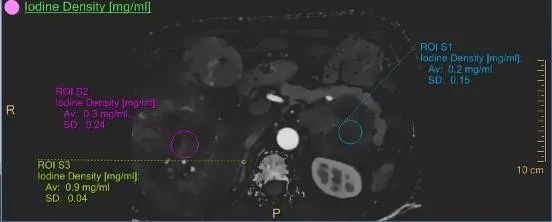

02.在腫瘤診斷方面

彩色光譜CT運(yùn)用獨(dú)特的雙層光譜探測器,擁有優(yōu)質(zhì)的超高清成像技術(shù),能早期發(fā)現(xiàn)隱匿病灶、實(shí)現(xiàn)腫瘤的良惡性和精準(zhǔn)分期、分級以及腫瘤活性的評估,同時(shí)能對多發(fā)病灶的同源性,淋巴結(jié)是否有轉(zhuǎn)移,指導(dǎo)臨床作出個(gè)性化、精準(zhǔn)的治療方案。